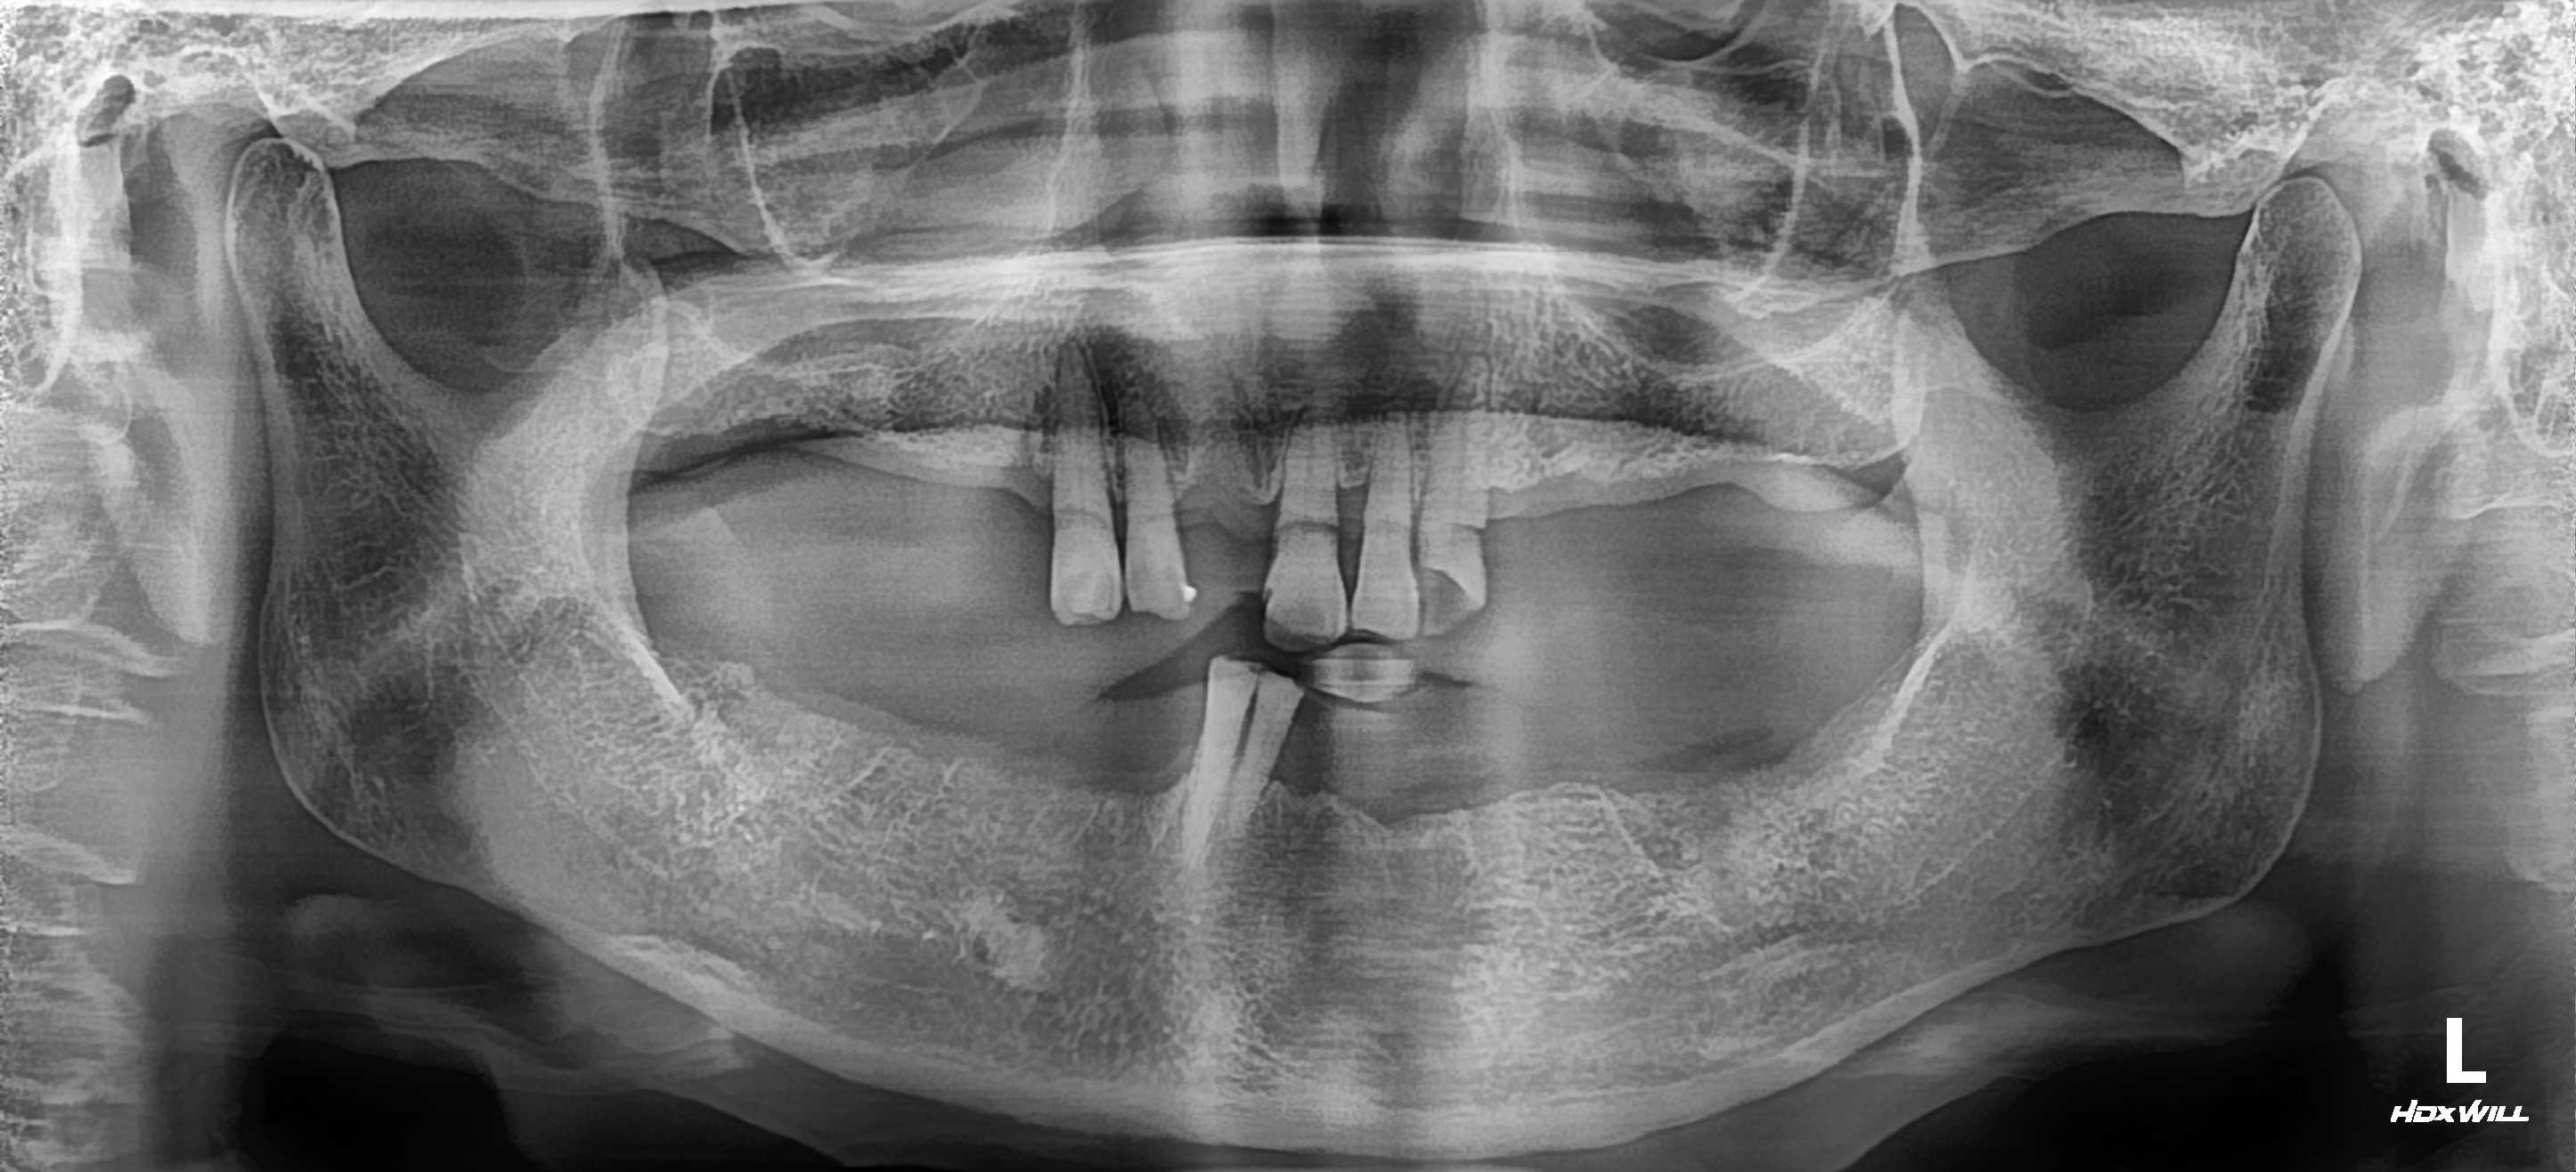

[치아교정] 치아교정 + 임플란트 통합치료

"이가 많이 썩고 앞니가 반대로 물려요"

20대 구강위생상태가 나쁘고 치아가 가지런하지 못하여 관리가 되지 않아 치아우식(충치)이 생겨 치과에 내원하였습니다.

치과가 무섭지만 용기내어 오셔서 최대한 아름다운 미소를 찾아드리기 위해 통합적인 치료 계획을 세웠습니다.

전체적인 교정을 시행하고 우식치아 크라운 치료, 치아가 없는 부위는 임플란트 치료를 동시에 진행하셨습니다.